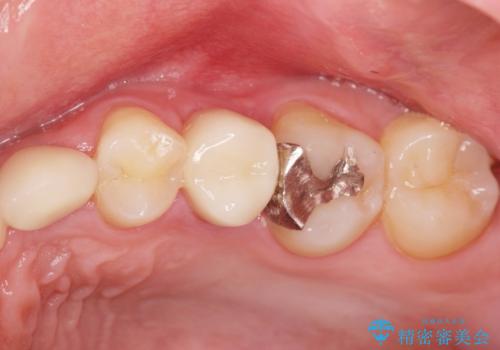

- ねじれてしまっている奥歯の矯正治療、銀歯のセラミック治療を求めて来院されました。

銀歯を外す前に部分矯正治療を行うことで歯のポジションを調整したのち、セラミック治療を行います。

90°ねじれてしまっていた歯を、矯正治療で治し、前後の歯の咬合関係も改善してしっかりと噛めるようになりました。